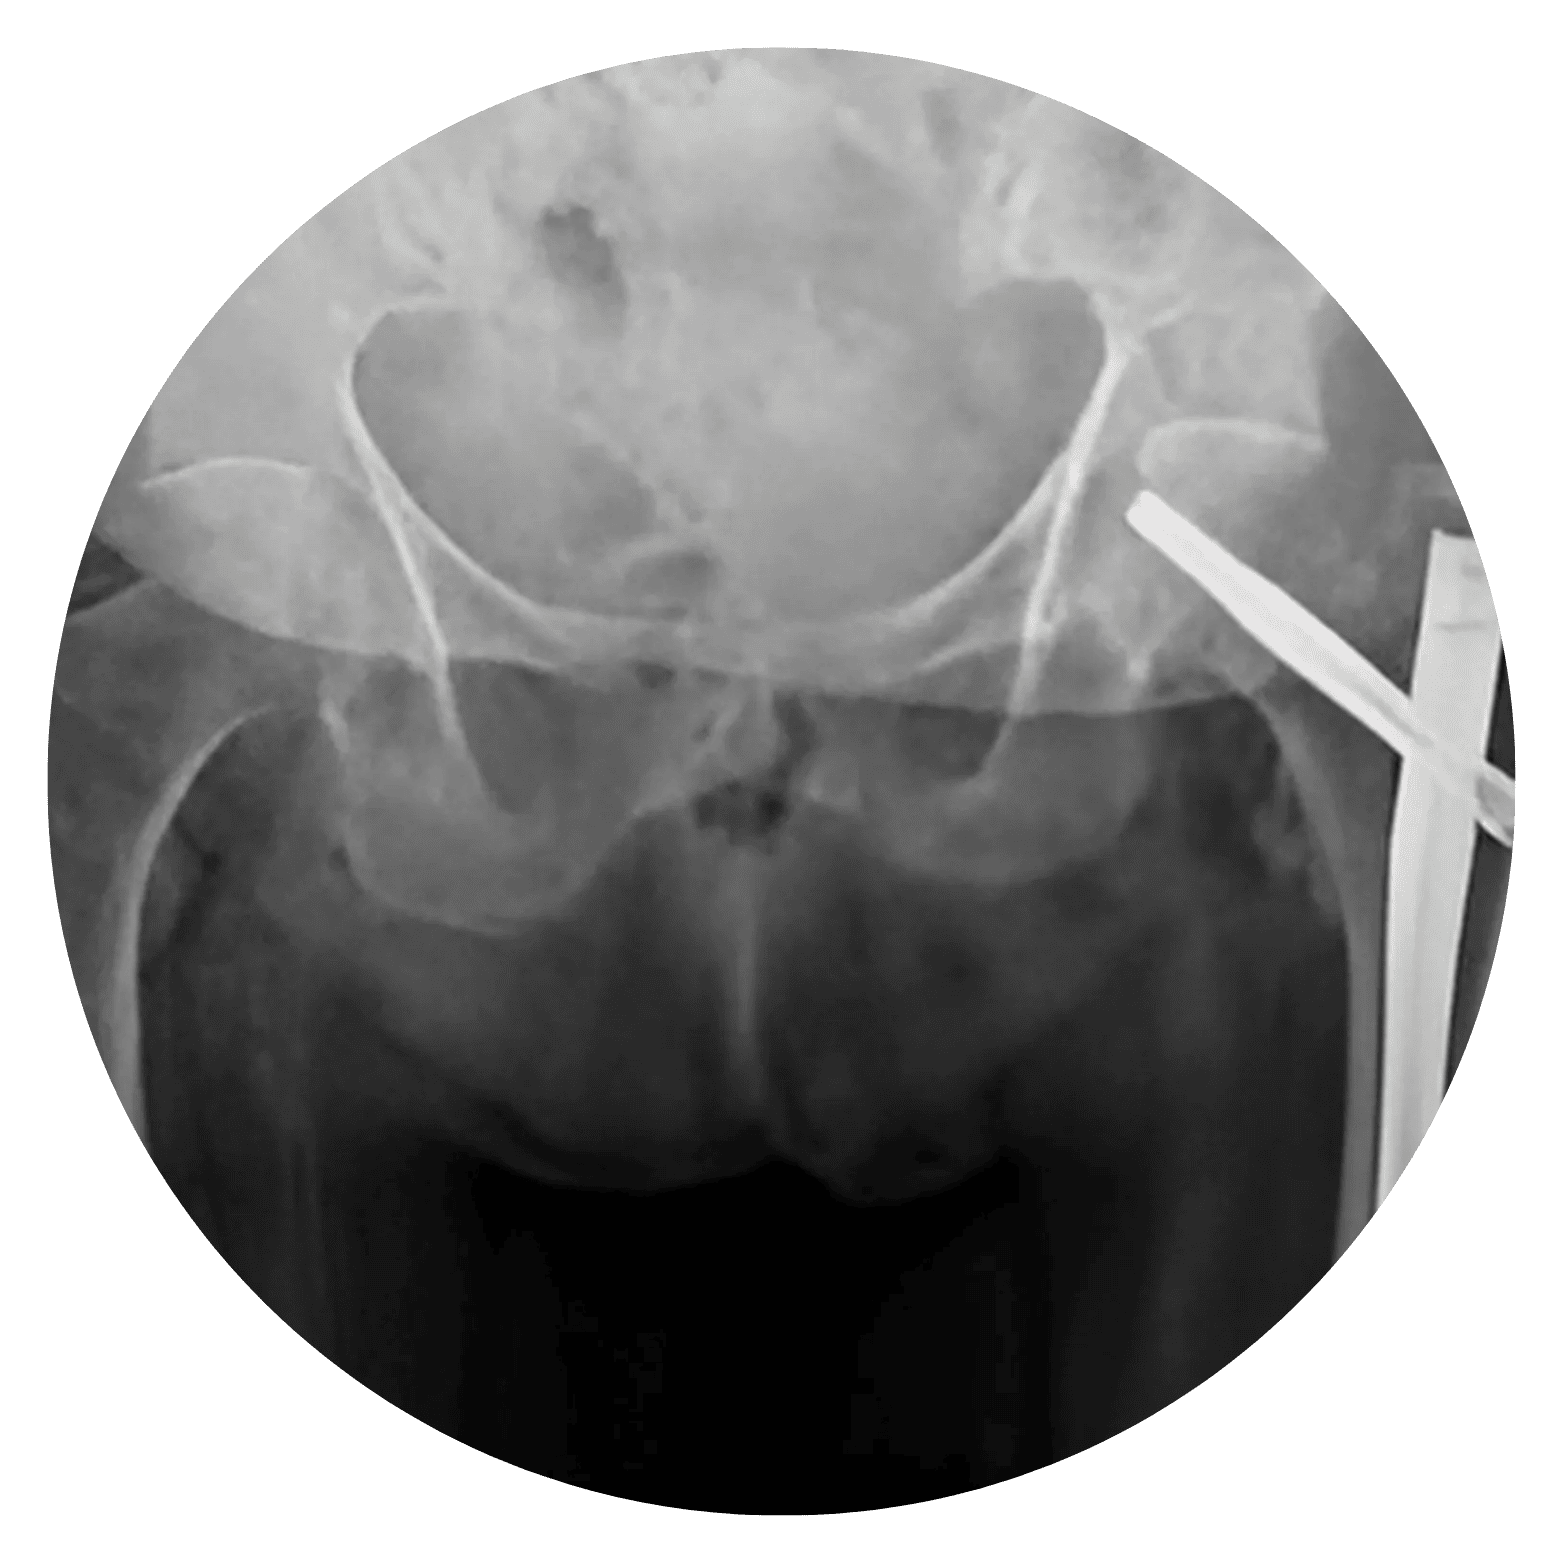

Hérnia de Disco Lombar Aquela dor insuportável na região lombar que impede o simples ato de amarrar os sapatos, ou uma pontada aguda que desce